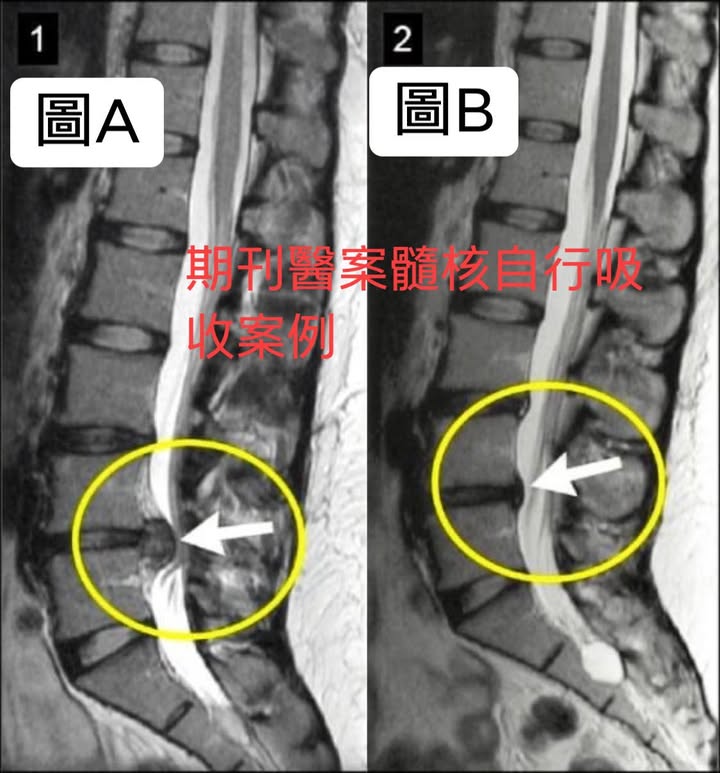

期刊中提到一名29女性因為嚴重腰痛跟腿痛就醫!她的腰椎核磁共振成像(MRI)顯示腰椎間盤巨大突出,導致實質椎管狹窄和神經根壓迫(圖A)。她選擇了保守療法物理治療,在短短5個月後第二次核磁共振成像顯示髓核有明顯吸收(圖B)